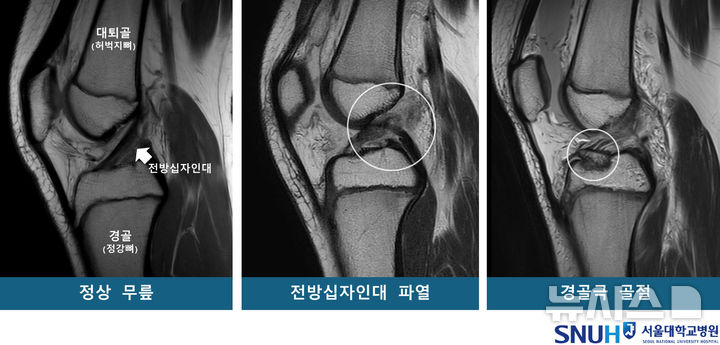

[서울=뉴시스] 정상 무릎 및 무릎 부상 환자의 MRI. (사진= 서울대병원 제고얘

연구팀은 소아청소년을 각 53명씩 ▲전방십자인대 파열군 ▲경골극 골절군 ▲대조군(정상 무릎)으로 구분하고 연령·성별을 매칭했다. 이후 자기공명영상장치(MRI)를 재구성한 3차원 영상을 바탕으로 14개의 해부학적 지표를 분석했다.